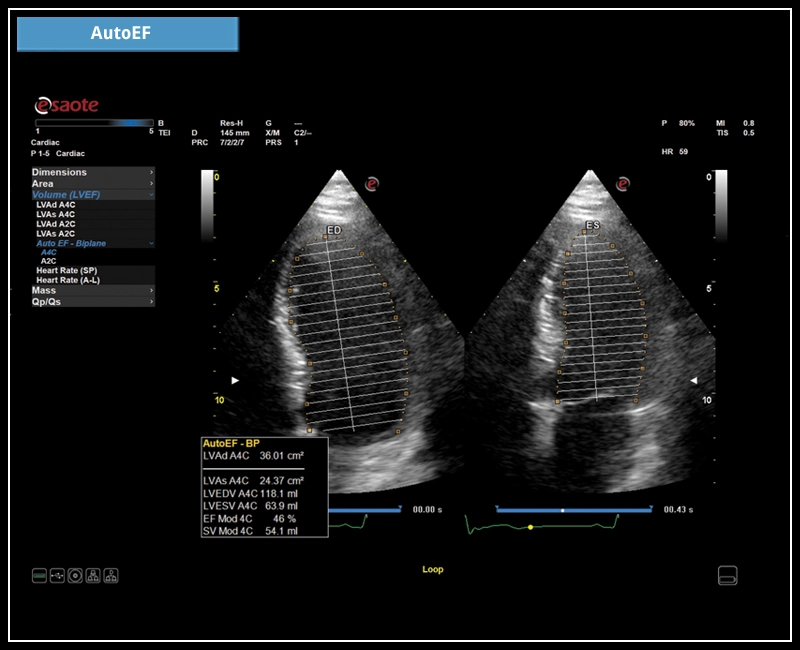

MyLab™E80 - AutoEF

MyLab™E80 - AutoEF

MyLab™Omega eXP - AutoEF

MyLab™Omega eXP - AutoEF

MyLab™X8 Platform - Zero-click EF measurement with Uterus - XLight 3D/4D exploration AutoEF

MyLab™X8 Platform - Zero-click EF measurement with Uterus - XLight 3D/4D exploration AutoEF

MyLab™X90 - AutoEF Automatic Ejection fraction assessment of the left ventricle

MyLab™X90 - AutoEF Automatic Ejection fraction assessment of the left ventricle

MyLab™X5 - AutoEF

MyLab™X5 - AutoEF

MyLab™X6 - AutoEF

MyLab™X6 - AutoEF

MyLab™X7 - AutoEF

MyLab™X7 - AutoEF

MyLab™Omega - Zero-Click AutoEF

MyLab™Omega - Zero-Click AutoEF

MyLab™A50 - AutoEF

MyLab™A50 - AutoEF

MyLab™A70 - AutoEF

MyLab™A70 - AutoEF